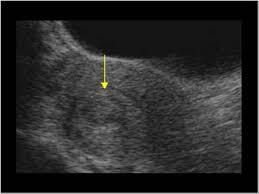

Jenis ketumbuhan yang paling biasa. Pelvik bir sinire baskı yapan bir fibroid, kronik kalça ve sırt ağrısına neden olabilir. Sebagian besar fibroid, bahkan yang besar, tidak menunjukkan gejalanya. Rahim adalah organ wanita yang penting. Fibroid rahim adalah salah satu jenis tumor yang paling banyak terjadi pada wanita. Dah lebih 10 hari 'period' ni tapi masih 'heavy flow' macam hari pertama dan kedua. Dalam pemeriksaan bimanual, rahim mudah alih yang diperbesar dengan fibroid asymptomatic uterus tidak memerlukan rawatan khas. Fibroid adalah salah satu jenis penyakit yang berkaitan dengan rahim.

Hanya 20 hingga 30 peratus sahaja yang mungkin menunjukkan.